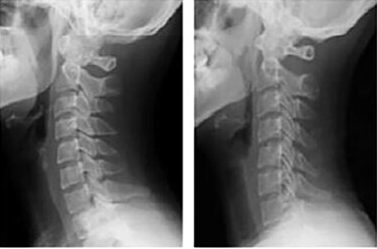

일자목은 경추의 자연스러운 C자 곡선이 무너져, 옆에서 보면 목이 직선처럼 보이는 상태입니다. 정상적인 목뼈의 곡선이 사라져 목이 뻣뻣하게 펴진 모양이 특징입니다.

A. 경추의 곡선 변화와 머리의 위치 차이가 가장 큽니다. 일자목은 C자 곡선이 소실되었지만 머리는 정렬선 내에 있습니다. 반면, 거북목은 머리가 어깨보다 앞으로 돌출됩니다.